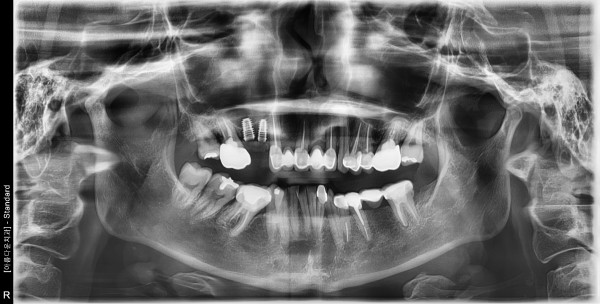

50세 여자 상악 구치부 뼈 이식후 임플란트 식립